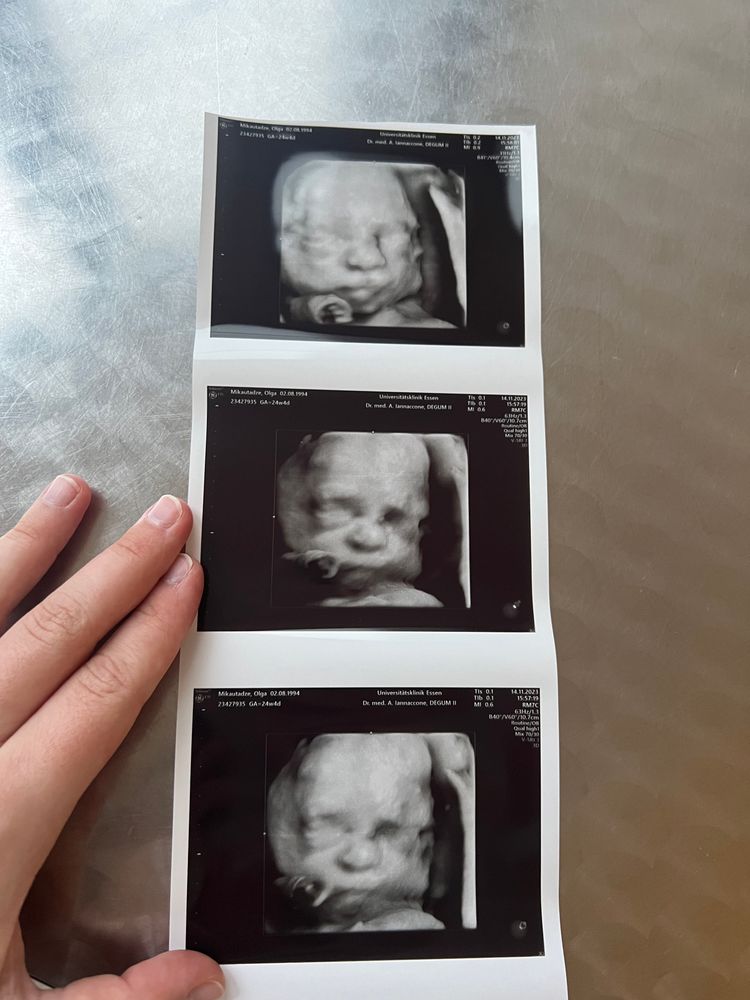

Какой сладкий малыш❤️пусть всё будет хорошо!!!и малышик родится в свой срок!❤️